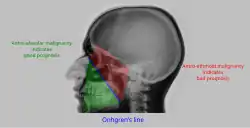

| Malignancy |

![]()